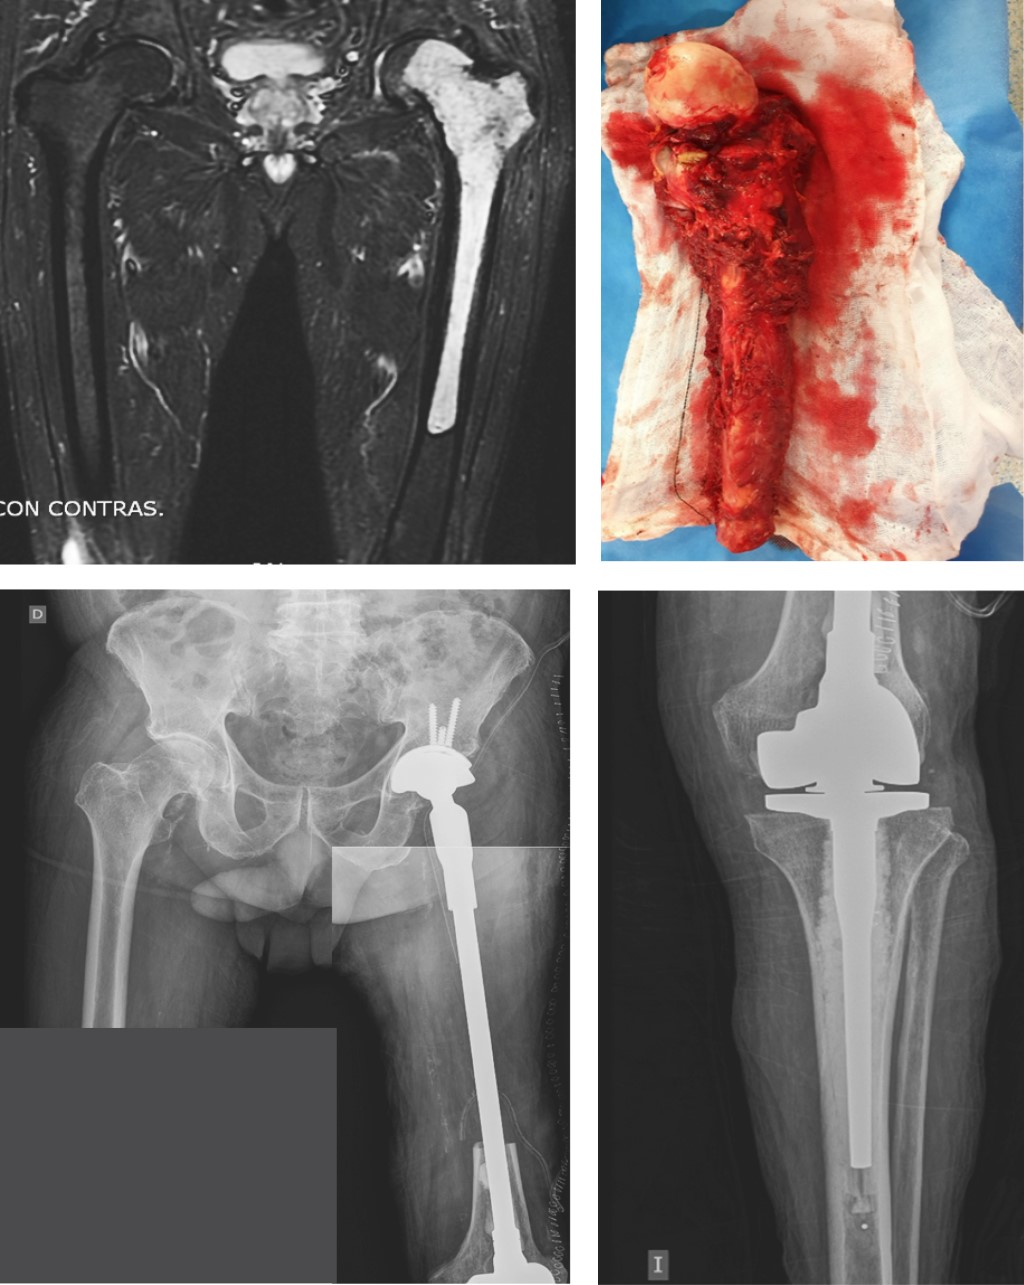

La reconstrucción tras la resección tumoral en los tumores pélvicos (nueve pacientes) se llevó a cabo mediante prótesis de anclaje ilíaco tipo "cucurucho de helado" (Coned®; Stanmore Worldwide Ltd, Elstree, UK) en siete casos y en los dos pacientes restantes se utilizaron prótesis pélvicas a medida con vástagos femorales modulares (Figura 2). En el resto de las localizaciones se utilizaron en todas ellas megaprótesis modulares: megaprótesis de fémur proximal con artroplastía de cadera en 11 casos, de fémur distal con artroplastía de rodilla en tres casos de tumoraciones femorales y dos de tibia proximal y megaprótesis de fémur total en tres pacientes (Figura 3). Con respecto a la fijación, ocho megaprótesis fueron no cementadas (26.7%), mientras que el resto presentaban alguno de los componentes cementados (73.3%). En ocho de los pacientes con resección del fémur proximal se conservó el trocánter mayor mediante reanclaje al vástago femoral para conservar la acción de los rotadores de cadera y en dos pacientes intervenidos mediante megaprótesis de fémur total se mantuvo la porción distal del fémur para mantener la musculatura aductora (Figura 4).

Figura 2

Figura 3

Figura 4